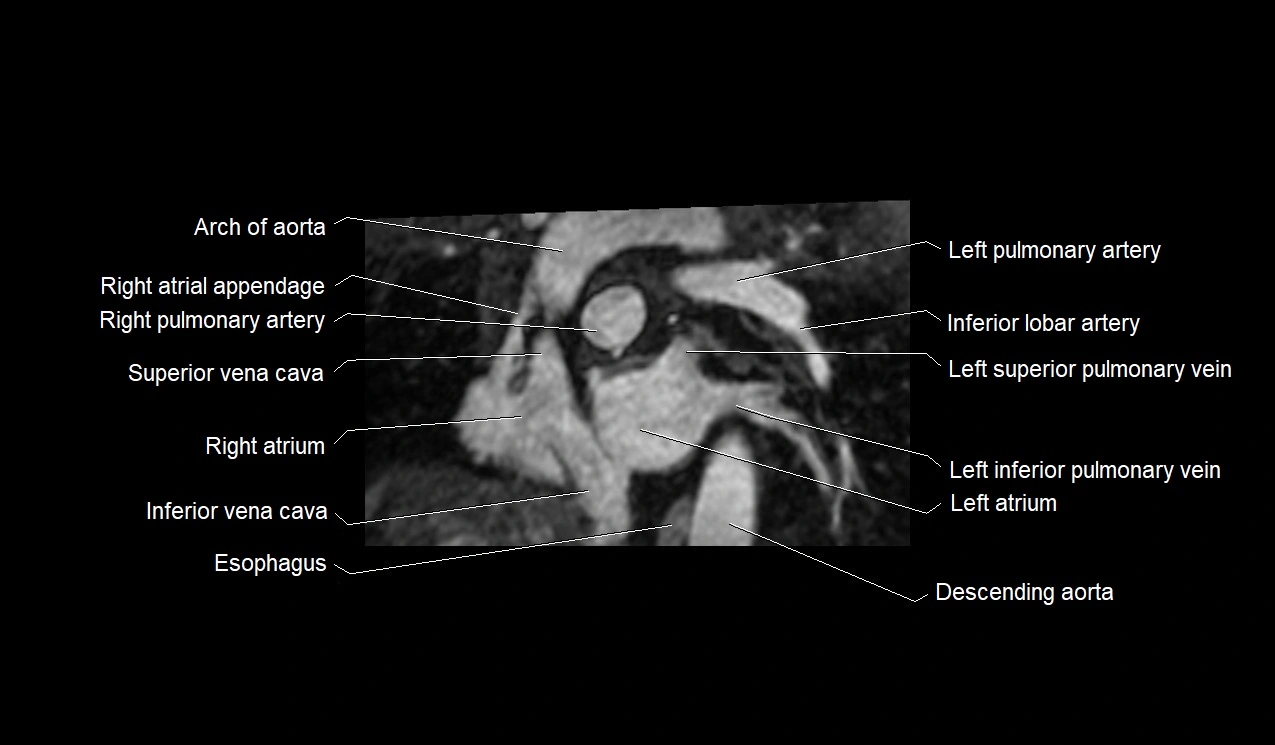

MRI image